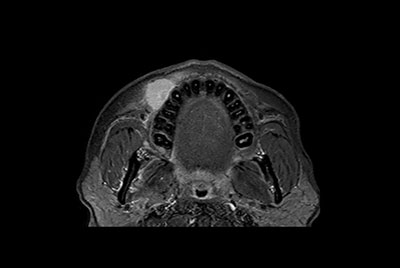

Soft Tissue of the neck